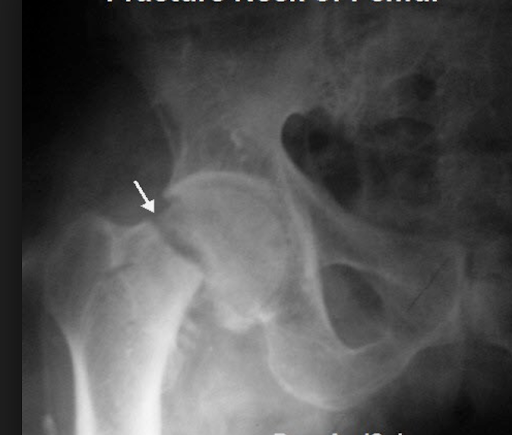

FASE2Q11